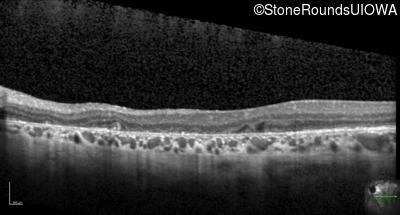

Optical Coherence Tomography - Right - 20/25 -2

Exemplar / OCT Stack